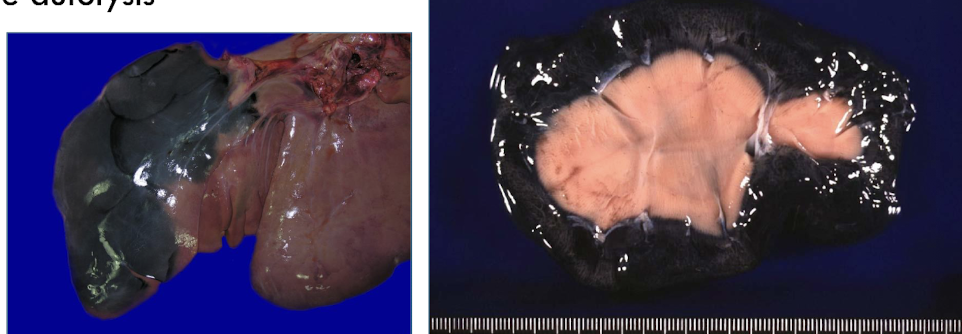

pseudomelanosis

blue-green to black discoloration of tissues by iron sulfide deposits

T/F: Pseudomelanosis deposits are actually melanin.

FALSE - not actually melanin

What reaction causes pseudomelanosis?

rx of hydrogen sulfide from putrefactive bacteria with iron in hemoglobin

What does pseudomelanosis signify?

severe autolysis